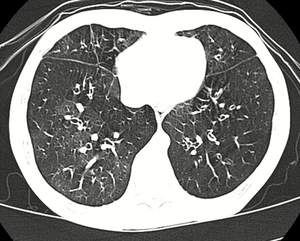

High resolution CT scan showing bronchiolitis obliterans with ground glass opacification, air trapping, and bronchial thickening[3] | |

Several tests are often needed to correctly diagnose bronchiolitis obliterans, including chest x-rays, diffusing capacity of the lung tests (DLCO), spirometry, lung volume tests, high-resolution CT (HRCT), and lung biopsy. Diffusing capacity of the lung (DLCO) tests are usually normal; people with early-stage BO are more likely to have normal DLCO. Spirometry tests usually show fixed airway obstructions and sometimes restriction, where the lungs can't expand fully. Lung volume tests may show hyperinflation (excessive air in lungs caused by air trapping). HRCT can also show air trapping when the person being scanned breathes out completely; it can also show thickening in the airway and haziness in the lungs. Transthoracic lung biopsies are preferable for diagnosis of constrictive BO compared to transbronchial biopsies; regardless of the type of biopsy, a diagnosis may only be achieved by examination of multiple samples.[20]